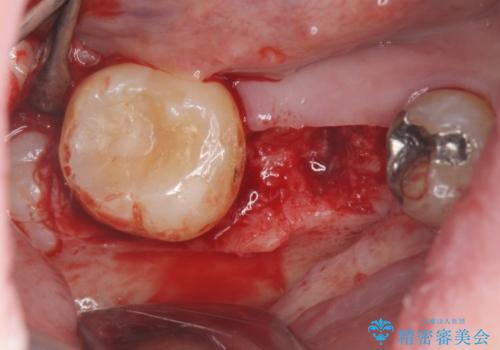

保存不可能な虫歯、インプラントによる機能回復

- 長年放置した虫歯痛み、治療を希望され来院されました。

右下の大臼歯は、虫歯が重度に進行し保存が不可能な状況です。

抜歯後、骨の吸収を造成にて回復しインプラント治療を進めます。